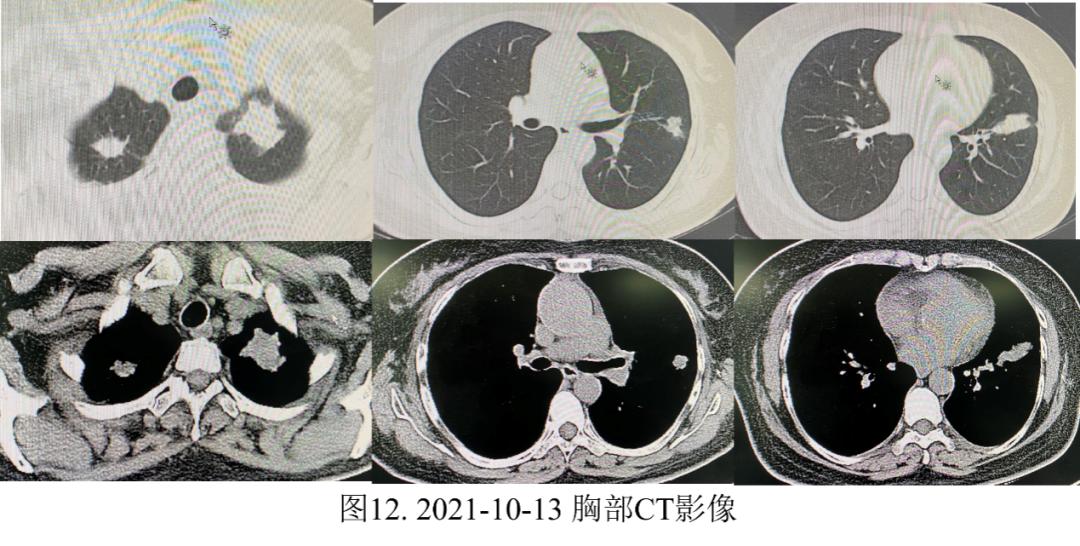

门诊给予克拉霉素缓释片 500mg qd治疗*12天。2021年10月13日,患者复查胸部CT示:双肺可见团片状高密度影,较前进展,左肺为著,较大者约3.2*2.8cm,可见分叶及毛刺,密度欠均匀,肺门及纵隔淋巴结未见肿大,未见胸腔积液(图12)。

为进一步确诊,患者2021年10月22日于上海肺科再次行肺穿刺活检术,病理示:CK(+),TTF-1(SPT24)(-),NapsinA(-),P40(+),CK5/6(+),Vimentin(-),ZEB1(-),SMA(-),Desmin(-),CD68(-),Ki-67(5%+),Syn(-),NUT(-),EBER(+)。(右上叶)细胞块包埋:结合HE及免疫组化结果考虑淋巴上皮癌(图13)。